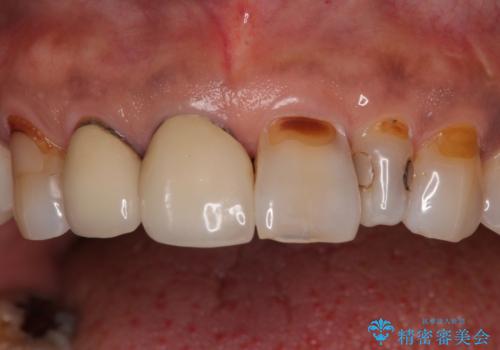

- 矮小歯である前歯がしみるとのことで来院された患者様です。

上顎前歯の歯肉ラインにエナメル質の欠損が認められ、そこが原因で冷たいものがしみている状態でした。

歯の大きさが小さいこと、隣の歯や反対側のセラミッククラウンの境目が見えていることなどから、前歯4本あるいは6本に対して、オールセラミッククラウンによる補綴治療をご提案しました。

見た目も大事だが、なるべく削りたくないとのことで、取り急ぎ4本を補綴治療し、今後犬歯の色などが気になることがあれば、追って対応することとしました。